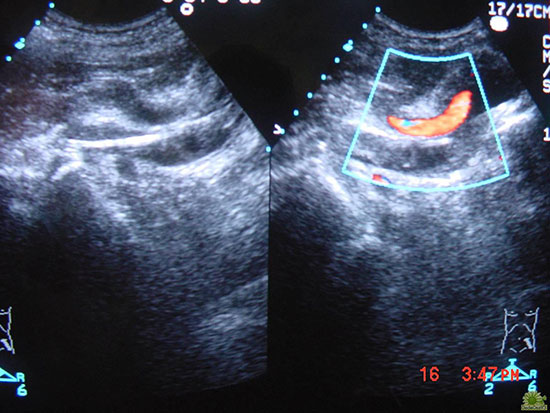

结合球囊扩张成形术

左图:髂静脉球囊扩张成形 右图:髂静脉再通